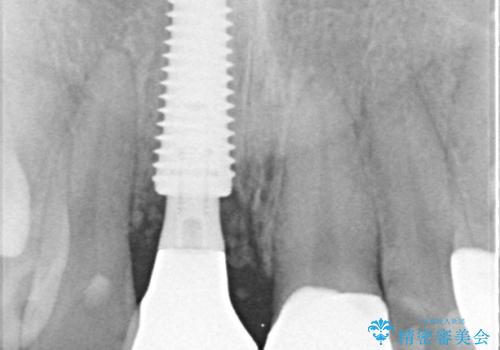

▶右上中切歯

抜歯後、即時インプラント埋入

審美性を考慮し、仮歯を即日装着

治療期間を最小限に抑えつつ、自然な前歯のラインと歯ぐきの形を維持